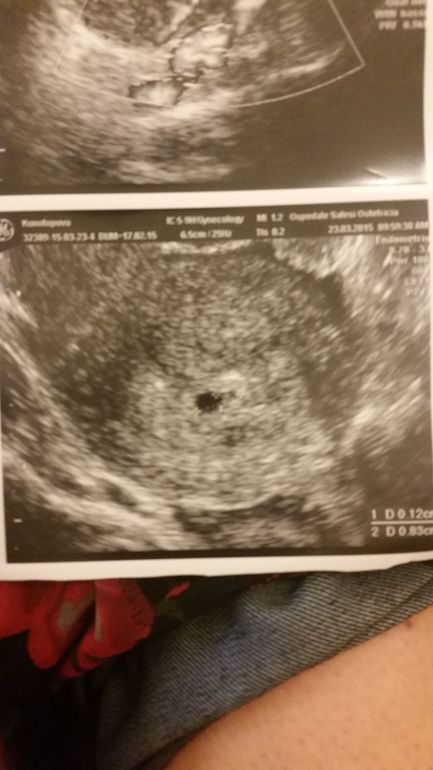

Как говорила моя доктор "вооот так черная точечка — это и есть ваш ребенок! Радуйтесь мамаша)))" Поздравляю!